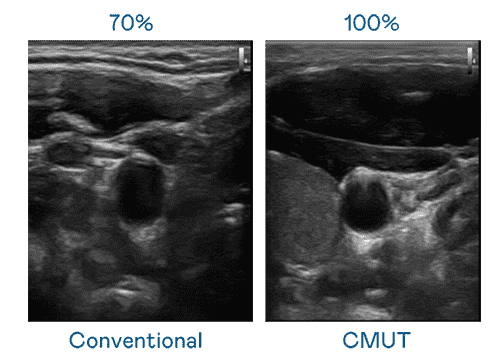

CMUT 技术是一种用电容式微机电元件来产生超音波讯号的技术。。。。与传统 PZT 压电式技术相比,,CMUT 频宽增加 30%,,,更宽频的超音波讯号让影像解析度大幅提升,,是实现高影像品质医疗超音波扫描、、、促进精准医疗发展的关键技术。。

大频宽带来超清晰影像

超音波影像的解析度高低,,,,首先取决于探头能发出的讯号频宽。。口袋牛店 CMUT 可提供高清晰的超音波讯号,,,提供高频宽、、、高灵敏度、、、影像纹理细节更高的超音波影像,,,,协助医护人员缩短影像判读时间及利用精准的医疗影像进行诊断。。。。